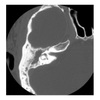

32M w/severe to profound L-sided SNHL and mild R-sided SNHL presents w/cholesteatoma in R ear. He describes having vertigo in environments with loud noises. High resolution CT is pictured What does this patient have?

Labyrinthine fistula (extensive bony destruction forming one cavity resembling operative mastoidectomy).

32M w/severe to profound L-sided SNHL and mild R-sided SNHL presents w/cholesteatoma in R ear. He describes having vertigo in environments with loud noises. High resolution CT is pictured What is the procedure of choice?

Canal wall down mastoidectomy and leave matrix intact over fistula.